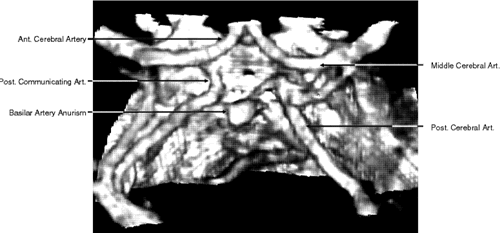

CTA of the intracranial vessels is an excellent tool for detecting cerebral aneurysm in patients with subarachnoid hemorrhage (Fig. 6). Compared with a standard cranial CT, it requires only a few more minutes to obtain detailed information about intracranial angiography. CTA obtained with multislice CT is a relatively new technology with promising implementations, but at present the clinical usefulness of multislice CT and CTA in neuroimaging is yet to be determined.

Fig. 6. Three-dimensional computed tomography angiography of the circle of Willis showing an aneurysm of the basilar artery.